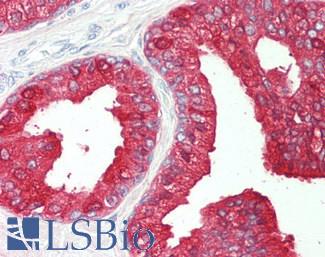

Anti-Smooth Muscle Actin antibody IHC of human prostate, smooth muscle. Immunohistochemistry of formalin-fixed, paraffin-embedded tissue after heat-induced antigen retrieval. Antibody LS-B7351 dilution 1:50.

SMMHC

Anti-Myosin, Smooth Muscle Heavy Chain antibody IHC of human prostate. Immunohistochemistry of formalin-fixed, paraffin-embedded tissue after heat-induced antigen retrieval. Antibody LS-B5148 concentration 20 ug/ml.